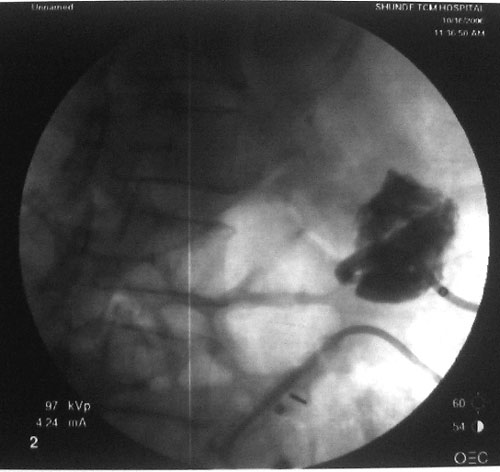

参照ct片,经皮穿刺,抽出透明液体60ml,随后置入引流管引流,囊液细胞学检查阴性,胰酶检查阴性。采用无水乙醇灌注治疗。4天后囊腔闭锁,无液体渗出,予以拔管。

置管后造影,显示囊腔直径约5cm,囊壁光整,正位、双斜位造影均未见造影剂外溢,与胰腺无交通